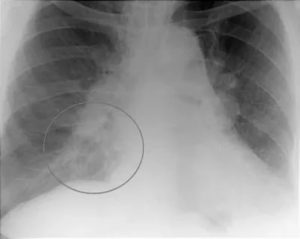

Локализация периферического новообразования значительно отличается от центрального. Расположение опухоли на наружной части легкого дает более четкую и яркую картину. На рентгенологическом снимке видны темные тени с признаками распада тканей.

По локализации периферический рак легкого значительно отличается от центрального. Очаг поражения тканей располагается на поверхности органа, поэтому проявляется четче. Внешний вид такого типа рака легкого на рентгене стандартный — темная тень с признаками распада тканей.

Видимость метастазов в легких на рентгене достаточно хорошая. В отличие от первичных опухолей, такие новообразования всегда множественные. По внешнему виду затемнения характеризуются как негомогенные структуры на поверхности или в толще органов, с нечетким краем и неправильной формой.

На начальной стадии метастазы определяются как множественные узелки.

При прогрессировании метастатического процесса рентгеновский снимок легких при раке обнаруживает распространенное поражение тканей, схожее с диссеминированной формой туберкулеза — пятна могут сливаться, образуя обширные затемнения. На последних стадиях на снимках становятся видны некротические очаги с распадающимися тканями, полости, наполненные экссудатом.

Наличие опухоли на задней стенке легких Периферическая форма рака Полостная форма рака